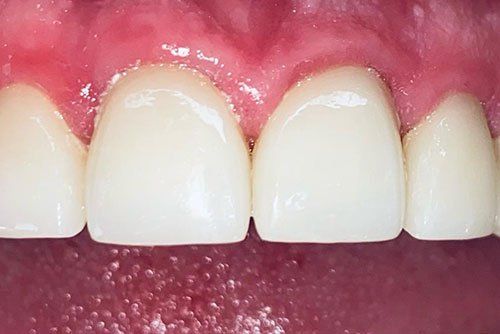

Dental Crowns Treatment

After Results

Joshua had broken down teeth that needed crowns. He wanted to renew his smile along with fixing his teeth!